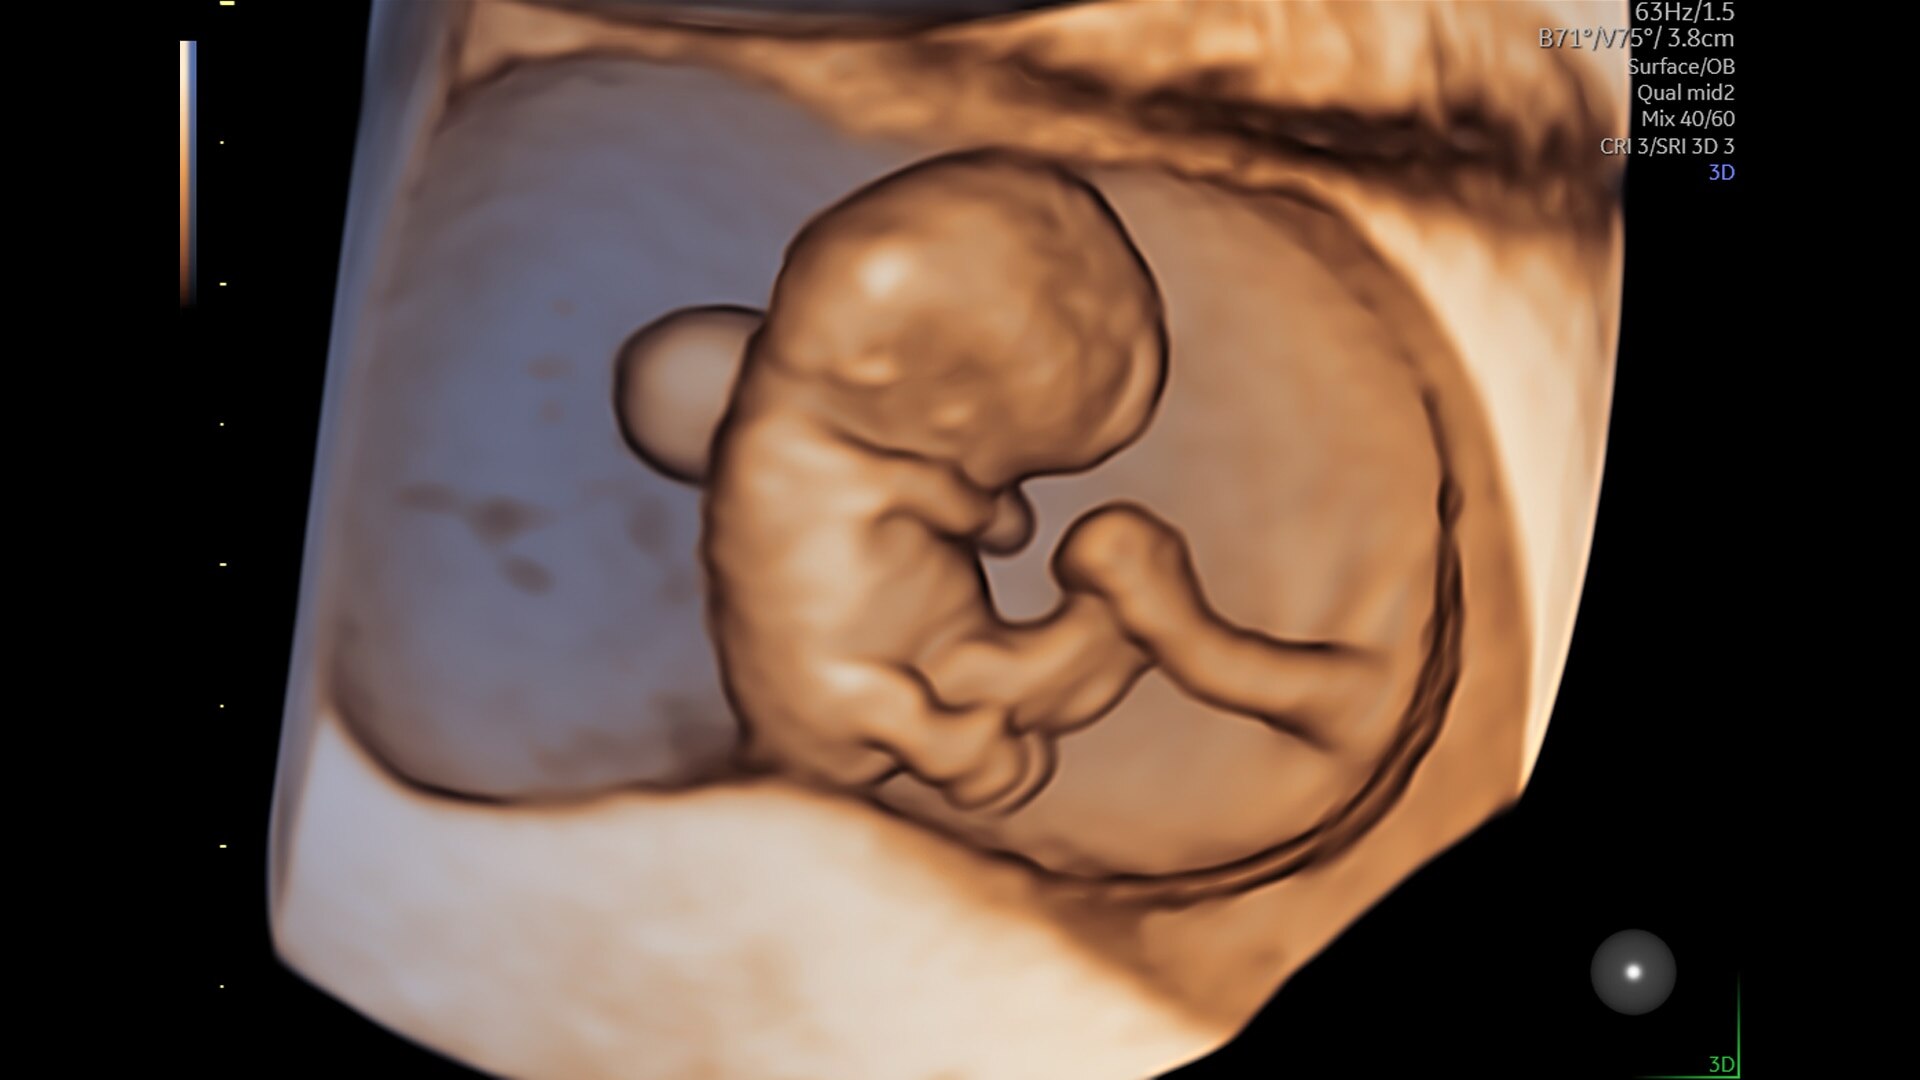

Advanced beamforming capabilities work in harmony with expert-level probes to deliver faster processing speeds and frame rates for enhanced detail and contrast resolution, greater color quality and sensitivity, and exceptional 3D/4D.

Fast, easy 3D-like blood flow visualization

Next level color Doppler delivers exceptional sensitivity for easy, fast visualization of blood flow, revealing even the tiniest vessels.

3-radiantflow-clinical-image-ci-en